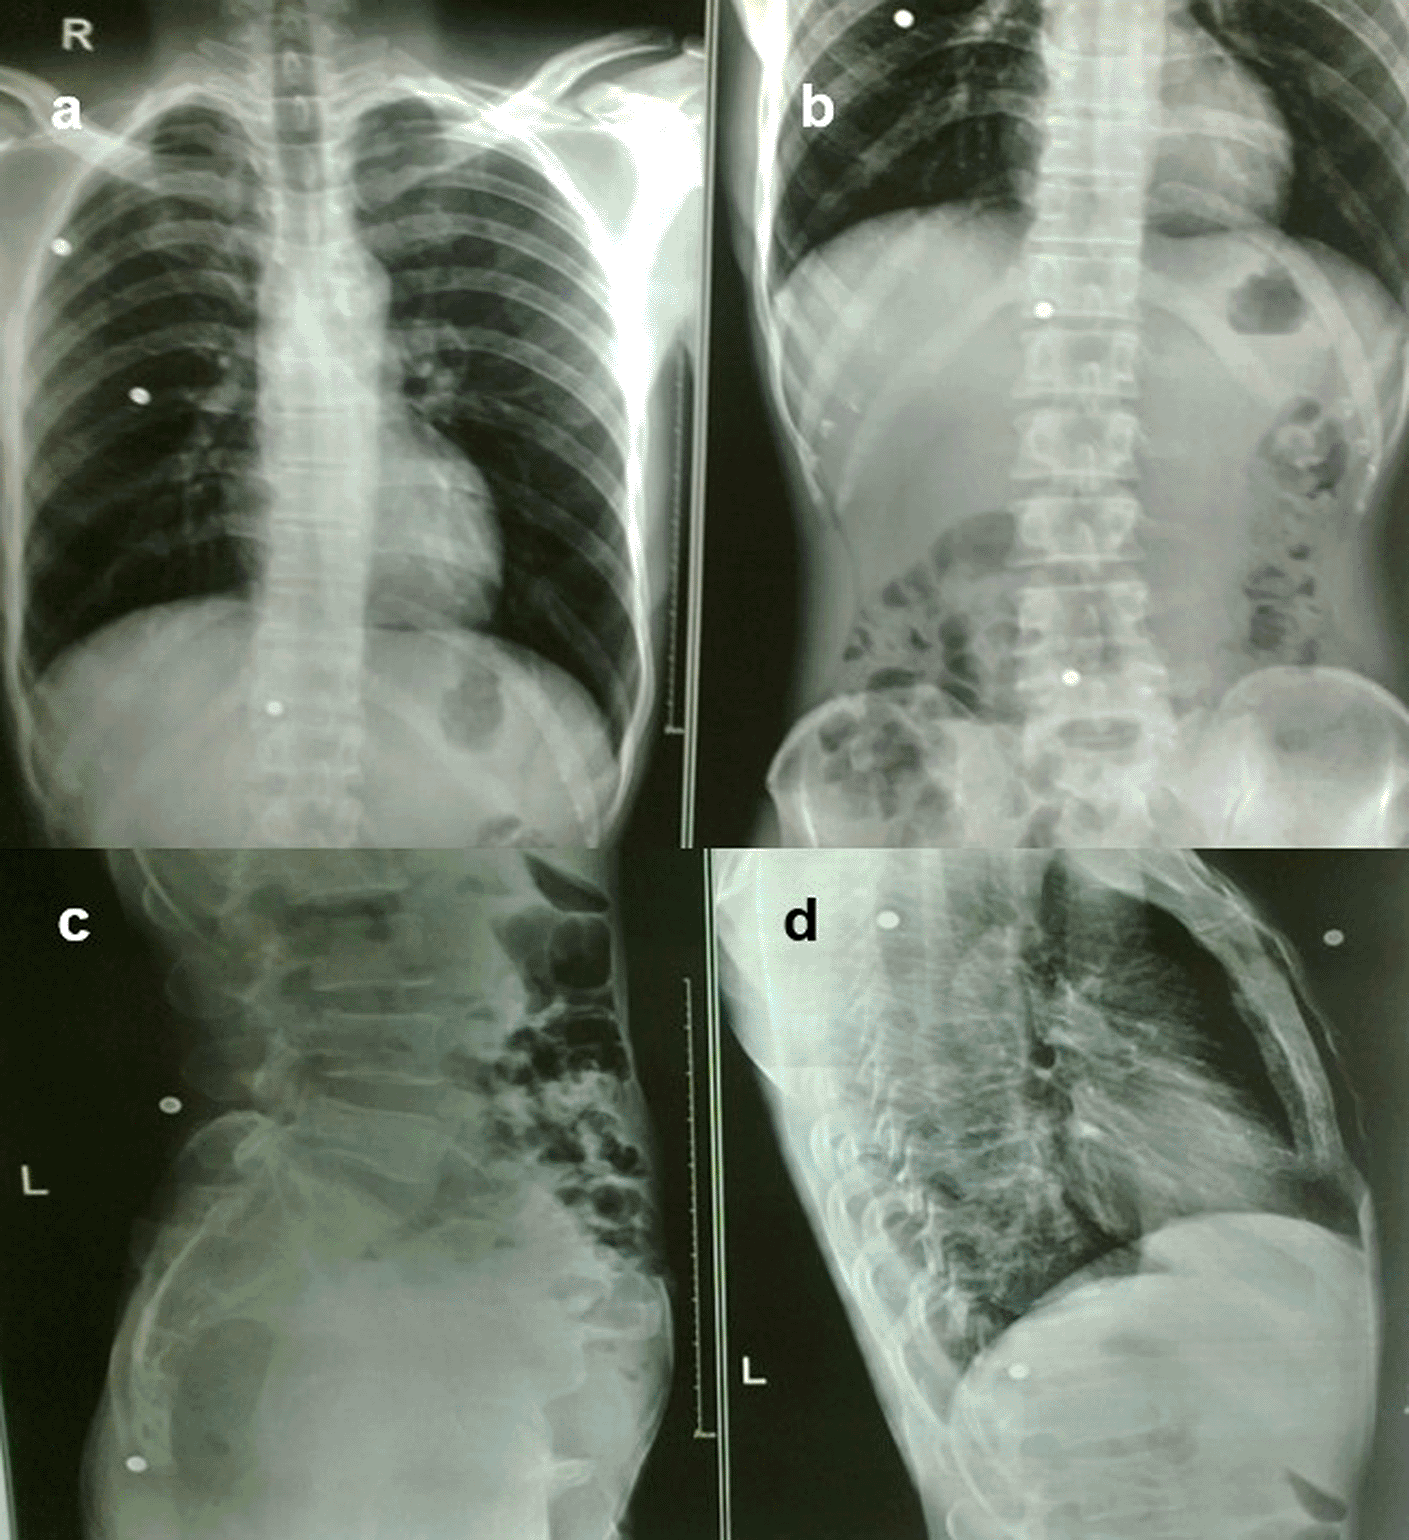

Case 9: A 37-year-old man had a history of bullet injuries. Radiographs of the chest and abdomen in frontal and lateral views revealed multiple pellets in the subcutaneous soft tissue of the thorax and abdomen.

The gauge of a shotgun pellet determines its size, the higher the number, the smaller the pellet. Serious soft tissue and bone damage can result from the combined mass striking a target close to the gun barrel (Figure 9a-d). Because steel pellets are ferromagnetic, they could move dangerously if such a patient with embedded steel pellets was exposed to a magnetic field, making magnetic resonance imaging potentially dangerous.2